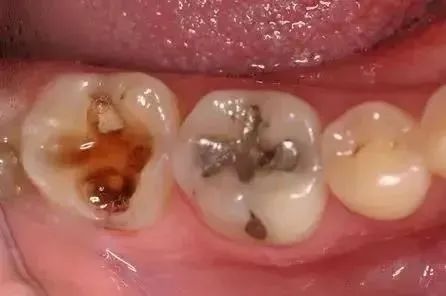

龋齿(蛀牙)发展三部曲:

浅龋:细菌只附在牙釉质层,初期表现为牙釉质面上有褐色或黑褐色的斑块,一般无症状,在检查时下被发现。

中龋:细菌已经攻到牙本质层了,这种情况下,有可能一开始会感觉到酸痛,但是过一段时间就慢慢没那么明显了。

深龋:细菌攻破牙本质快接近牙髓的时候,就比较严重了,一般遇到冷热酸甜都是很酸痛或刺痛。严重的还会扩散到牙周,引发牙周感染。